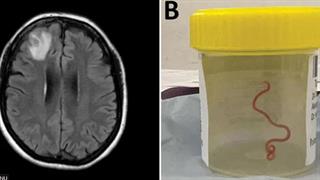

Παγκόσμια πρωτιά: Ζωντανό σκουλήκι 8 εκατοστών σε εγκέφαλο γυναίκας

Τι σχολιάζουν οι Αυστραλοί επιστήμονες που αντιμετώπισαν το πρωτόγνωρο αυτό περιστατικό.